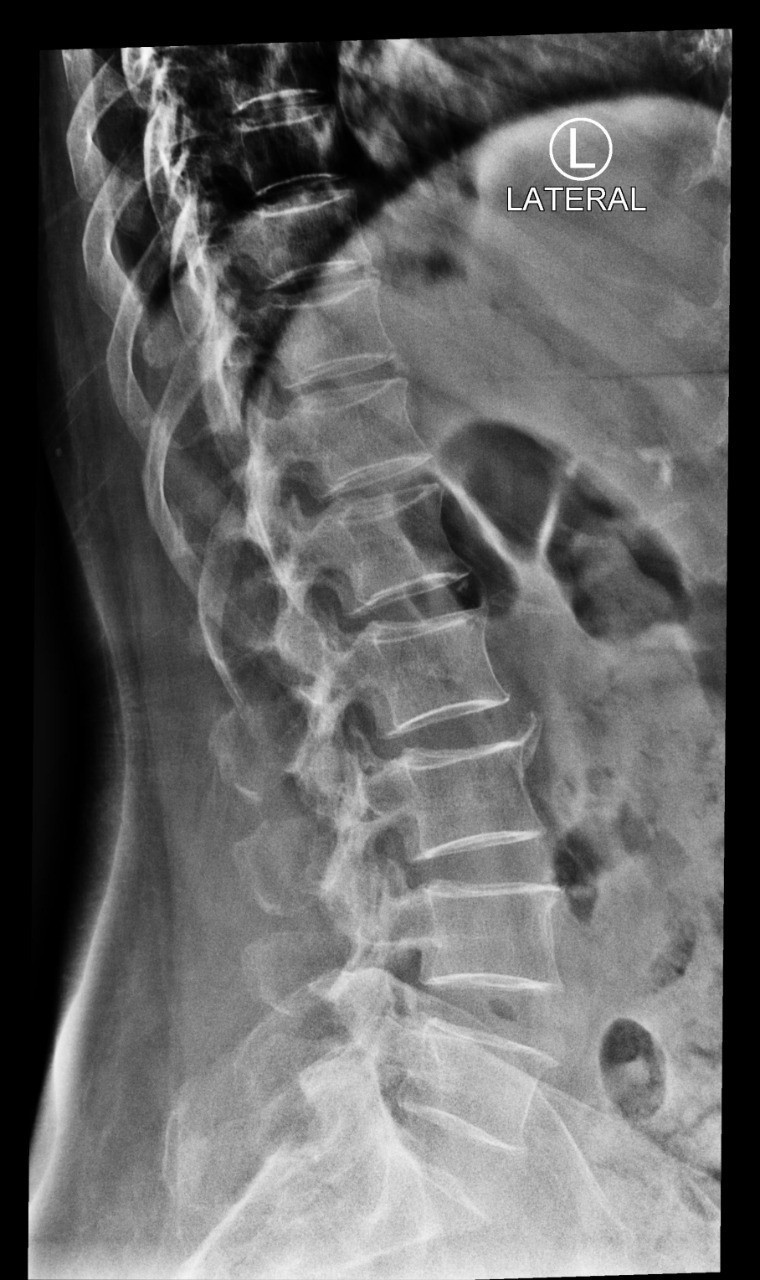

في كل يوم اسمع أمي ومن هم حولي من كبار السن يعانون من الآم مستمرة في العظام تحديدًا في منتصف الظهر والورك الأيمن والأيسر والركبتين، فهذه المناطق أرى أن أكثر كبار السن يشتكون منها. المراجعات الخاصة بالمسشتفى بلا فائدة، الأدوية كذلك. تأثرت صحة أمي كثيرًا فلم تعد تمارس اعمالها كما في السابق ولم تعد حتى تقدر على طلوع الدرج ولا الجلوس كثيرًا. وهذه بعض صور الخاصة بأشعة العظام عندما تم فحصها